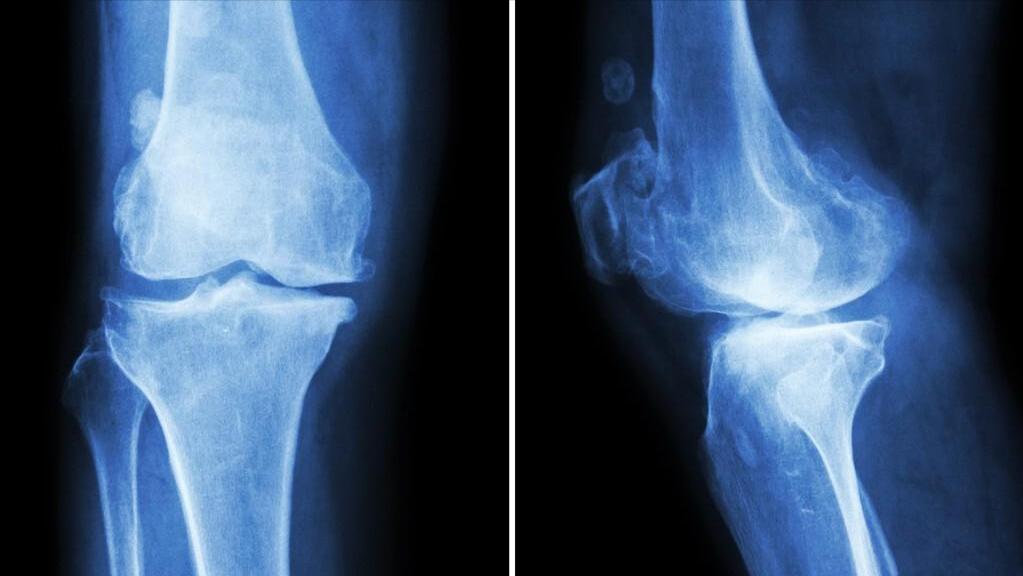

六、骨刺

很多时候人们并不知道自己长了骨刺,平时没有任何症状,只是去医院检查才发现。其实骨刺在中年老年人中很常见,主要长在关节中。但是只要是不影响人们正常生活的骨刺都是无害的。

骨刺学名叫做骨赘是因机体代偿反应自然产生的,骨刺的生长是一种正常的生理现象。骨刺在一些特殊人群例如久坐、肥胖或重体力劳动者中出现,而老年人多因骨质增生而生长骨刺。

正常的骨刺不会压迫刺激周围组织,且不会对身体产生任何不良影响,但如果骨刺增长过大就会对其他部位产生压迫,这可能引起疼痛以及炎症反应。另外如果骨刺过大则可能引起关节功能障碍等疾病,这种情况下才需要就医。